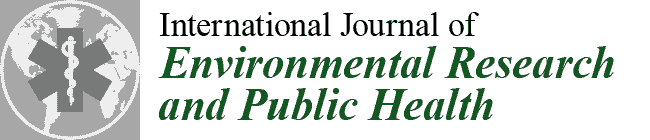

2.2. VOSTARS HMD-Based Surgical Navigation Platform and Template-Based Registration